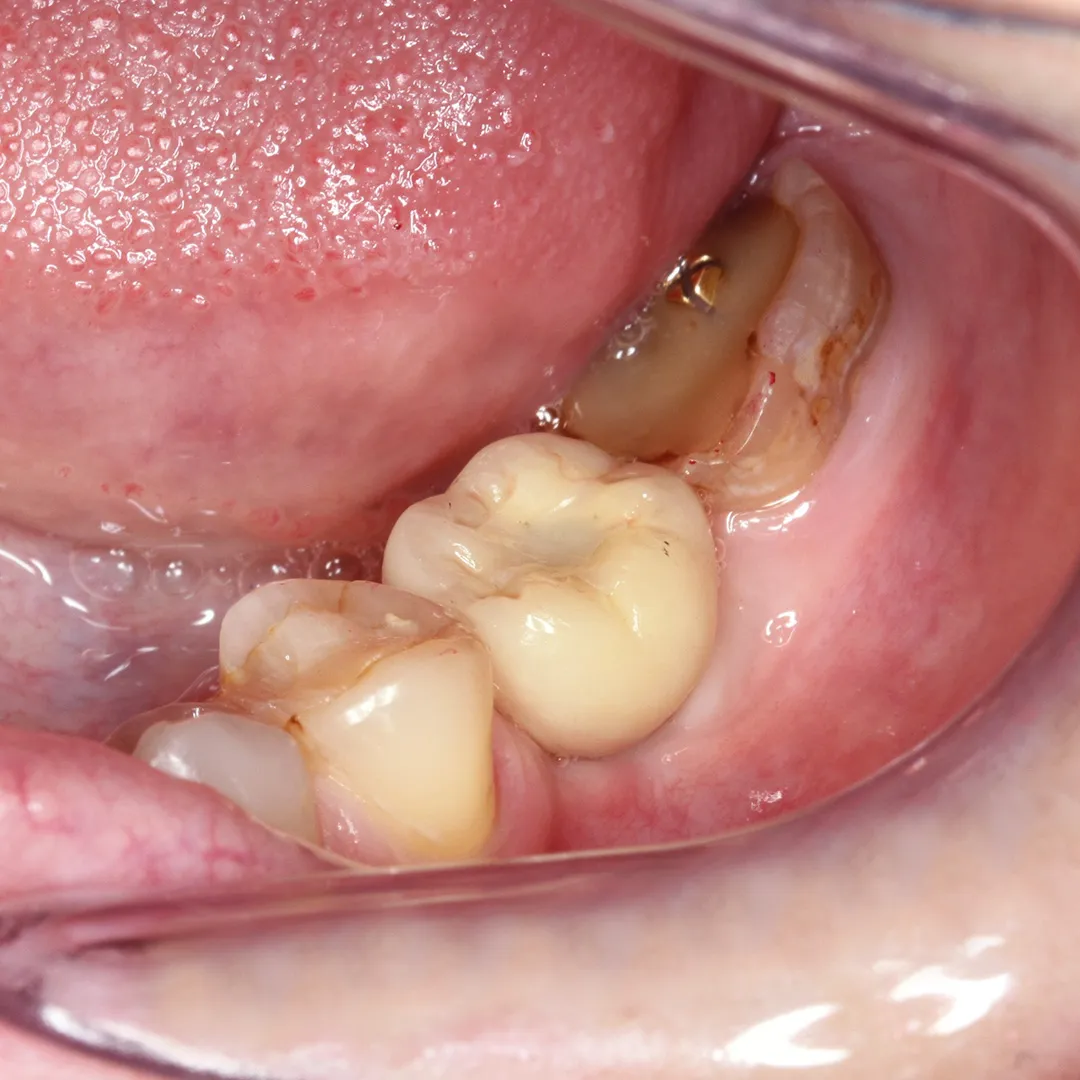

Установки импланта Alpha Bio в позицию зуба 4.6 «под ключ» для восстановления жевательной функцииСмотреть работуСрок лечения:30 минутСумма лечения:44 350 руб.

Удаление зуба в результате хронического периодонтита с одномоментным проведением имплантацииСмотреть работуСрок лечения:60 минутСумма лечения:74 970 руб.